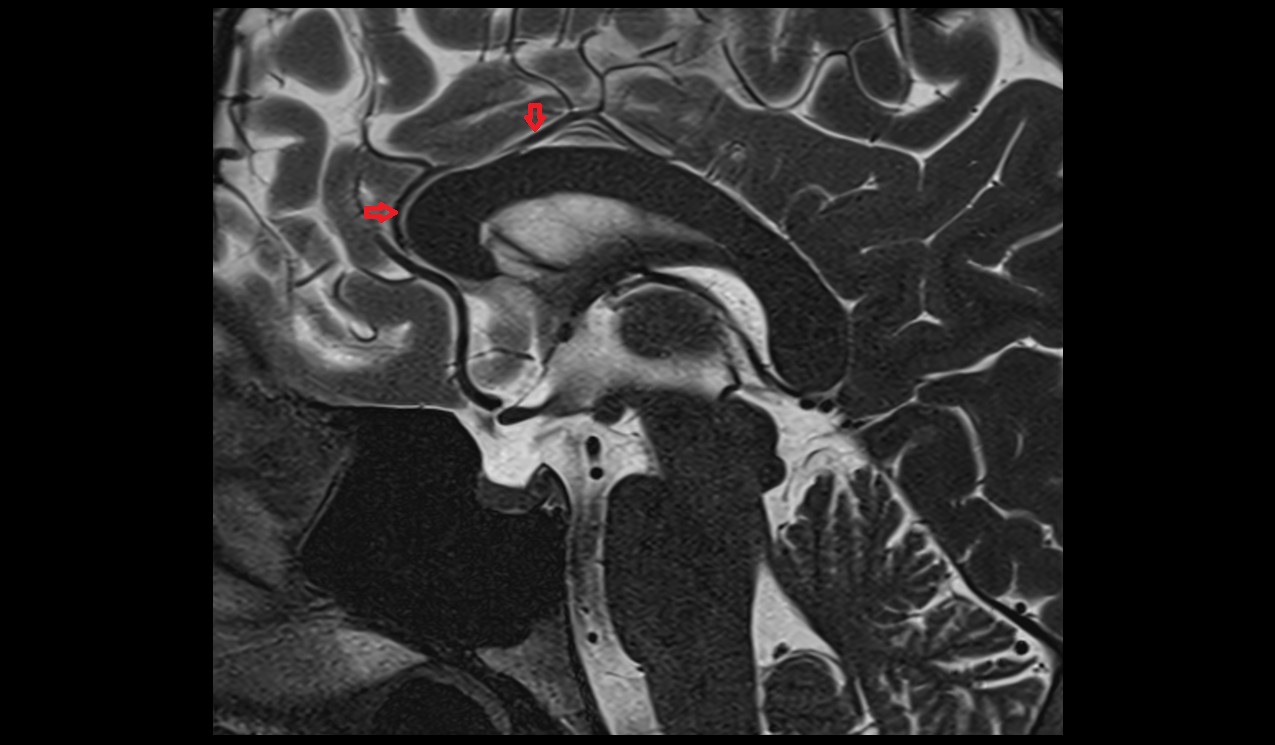

- Long medial striate artery